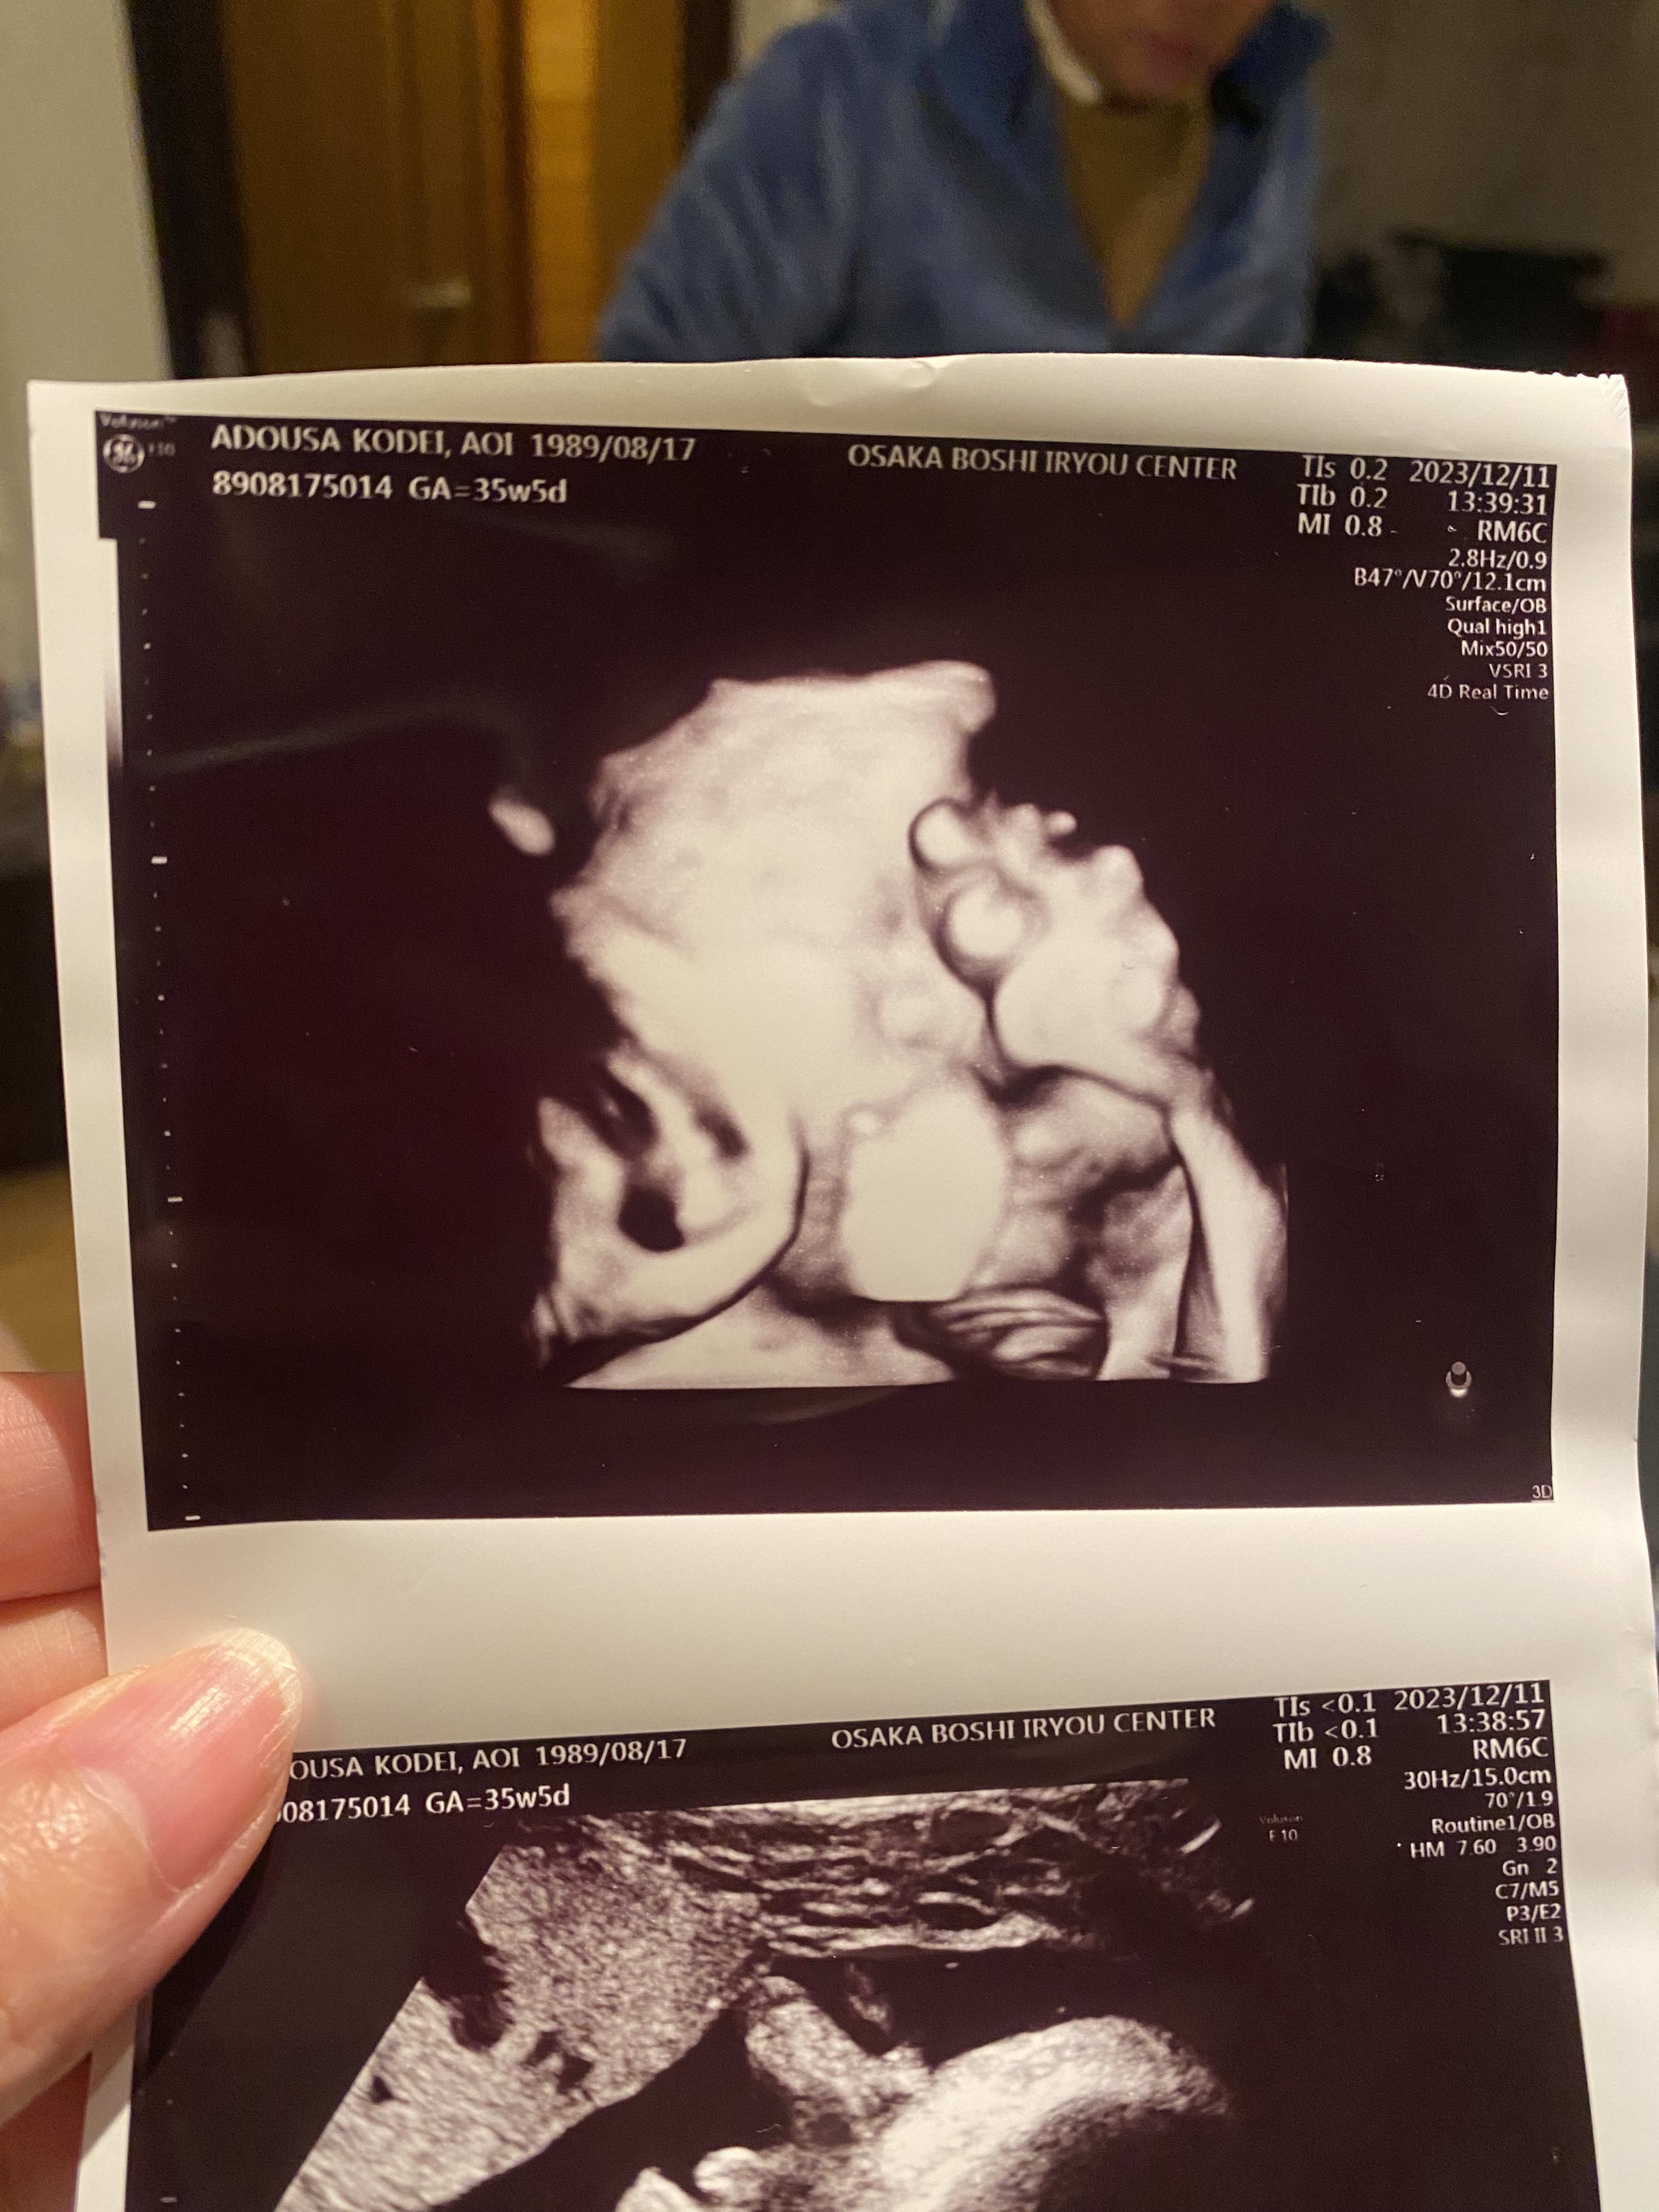

35週5日のエコー写真。 もうすぐ臨月!まだ臨月に入ってないのに、レオくんの推定体重は3025g!大きすぎて精密検査することになって不安だったけど、なにもなくてよかった〜 頬がふっくらしているのがエコー写真でわかる😂